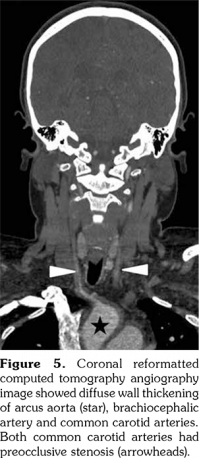

A 14-year-old female patient referred to our clinic with headache and dizziness for two weeks and loss of consciousness for about 10 minutes. On admission, the blood pressure was 90/60 mmHg and all peripheral pulses were palpable. Her body weight was above 97th percentile for her age and body mass index was 33. The fundus examination and other organ systems were essentially normal. Laboratory studies revealed erythrocyte sedimentation rate (ESR) as 108 mm/hour and C-reactive protein (CRP) as 7.5 mg/dL (0-0.8), while other measurements were normal. Urinalysis revealed microscopic hematuria and proteinuria of 31.9 mg/m2/hour in 24-hour urine collection. The cerebrospinal fluid examination showed no abnormalities. Cranial magnetic resonance imaging (MRI) showed multiple millimetric hyperintense deep white matter lesions on T2-weighted imaging (Figure 1). Intracranial and extracranial arteries were normal in magnetic resonance angiography (MRA). Renal biopsy findings were interpreted as FSGS (Figure 2). Patient was considered as cerebral vasculitis and incidental FSGS. Pulse methylprednisolone therapy for three consecutive days was initiated and continued with oral prednisolone. At four years of follow-up, proteinuria decreased to 5-15 mg/m2/hour, and ESR and CRP were normal. Repeated brain MRI and MRA examinations showed no new lesions. Four years later, at the age of 18, on a routine examination, both radial artery pulses were absent and the blood pressure could not be measured. Significant bruit was heard on the left carotid artery. Laboratory studies revealed ESR as 43 mm/hour and CRP as 2.46 mg/dL. Aortic MRA revealed diffuse wall thickening and contrast enhancement in the arcus aorta and its many main branches (Figure 3). Takayasu arteritis diagnosis was established according to the European League Against Rheumatism/ Paediatric Rheumatology International Trials Organisation/Paediatric Rheumatology European Society criteria.[2] Methotrexate was begun, and daily prednisolone was continued. Four months after the diagnosis of TA, left-sided hemiparesis developed. Brain MRI demonstrated a wide cerebral infarct at the right anterior vascular territory (Figure 4). Brain and neck computed tomography angiography showed total occlusion of the right internal carotid artery. Vascular involvement of the right common carotid artery was progressed to preocclusive stenosis. Diameters of the right anterior and middle cerebral arteries were thin and fed by the posterior and anterior communicating arteries (Figure 5). Tocilizumab treatment was started at 8 mg/kg every four weeks. At follow- up with 2.5 years of tocilizumab treatment, the patient's clinical condition improved slightly, and no new symptoms developed. A written informed consent was obtained from the patient.